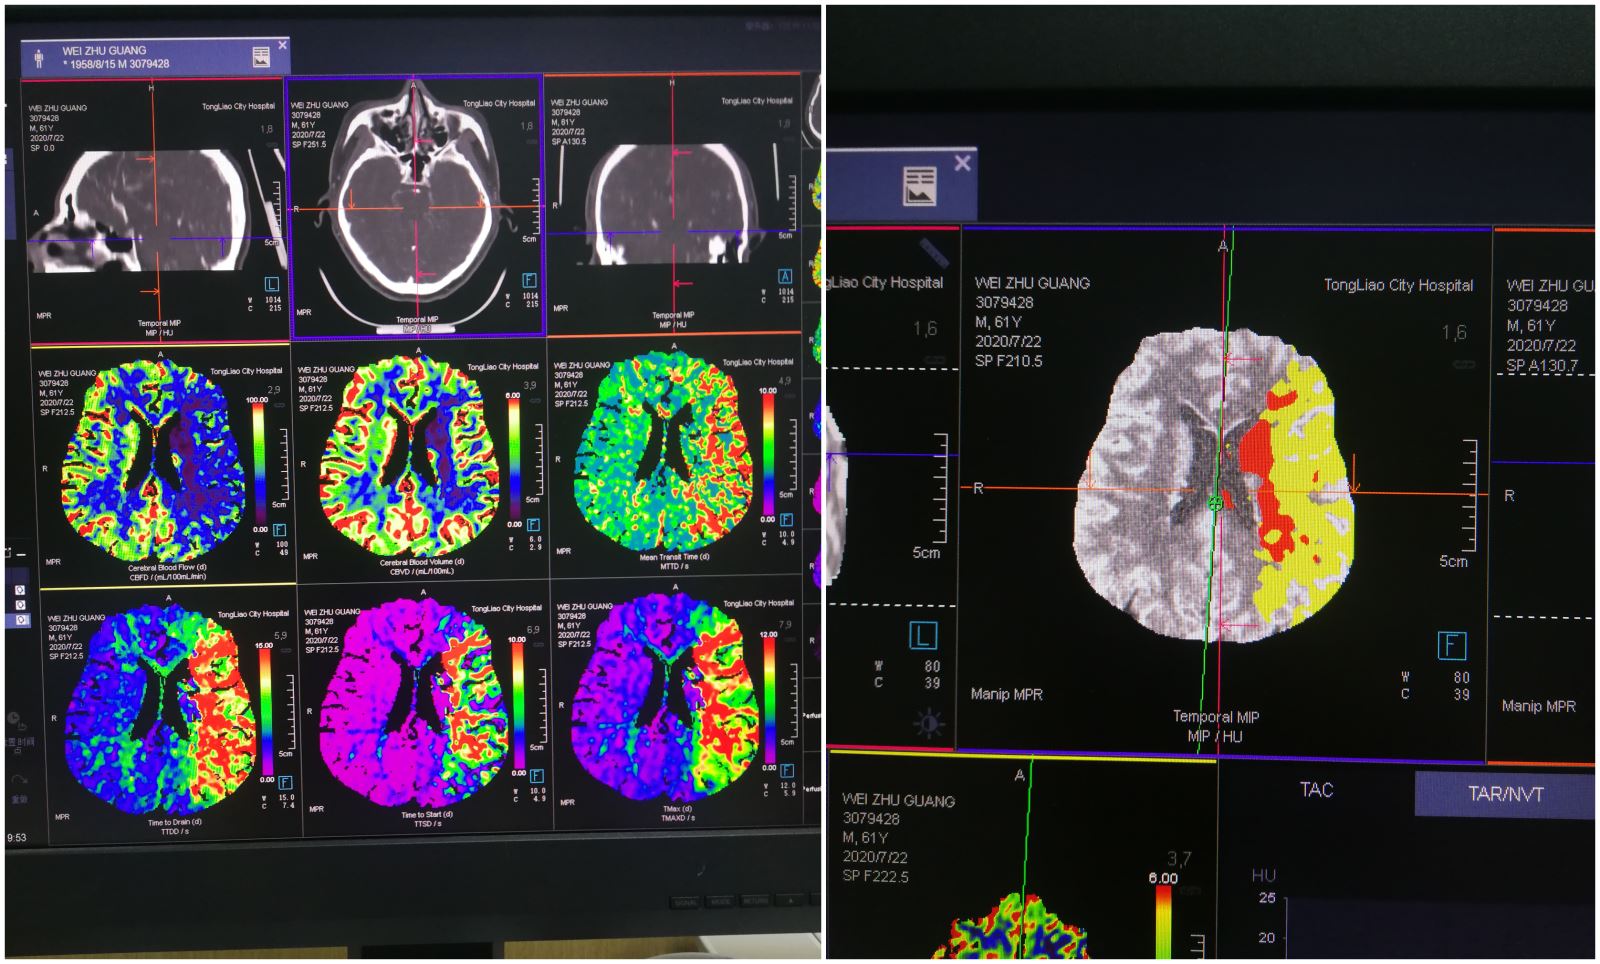

患者魏某,男性,61岁,于冲澡时出现失语,右侧肢体活动不灵后摔倒,急拨打120来院,我院立即开通卒中绿色通道,完善头部CT检查后初步诊断脑梗塞。急性脑梗塞致残、致死率极高,愈后功能恢复与发病时间密切相关,如不及时救治,预后极差。此时距离发病时间约有1小时,经家属同意后,神经内三科白塔娜医生立即给予患者阿替普酶紧急静脉溶栓治疗,并完善头部CTA+CTP检查,提示左侧大脑中动脉闭塞,与此同时通知介入导管室做好急诊手术准备。溶栓后再次评估NIHSS评分14分,患者临床症状改善不明显,在与家属充分沟通病情后,决定施行动脉取栓术,手术由神经内三科徐鹏医生主刀,李士伟医生协助。在为患者行全脑血管造影后,证实为左侧大脑中动脉闭塞,立即予以取栓术治疗。经过一个多小时的奋战成功将患者血栓取出,缺血区域血流迅速恢复畅通,缺血症状立即得到改善,取栓成功。患者术后恢复正常,取栓效果明显。